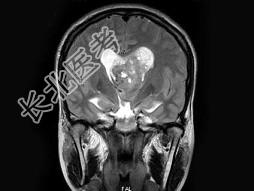

- 单项选择题男,32岁, 头痛呕吐半个月,MRI检查见脑室内占位, 最可能的诊断为 ( )

A、脉络膜丛乳头状瘤

B、室管膜瘤

C、髓母细胞瘤

D、脑膜瘤

E、未见异常